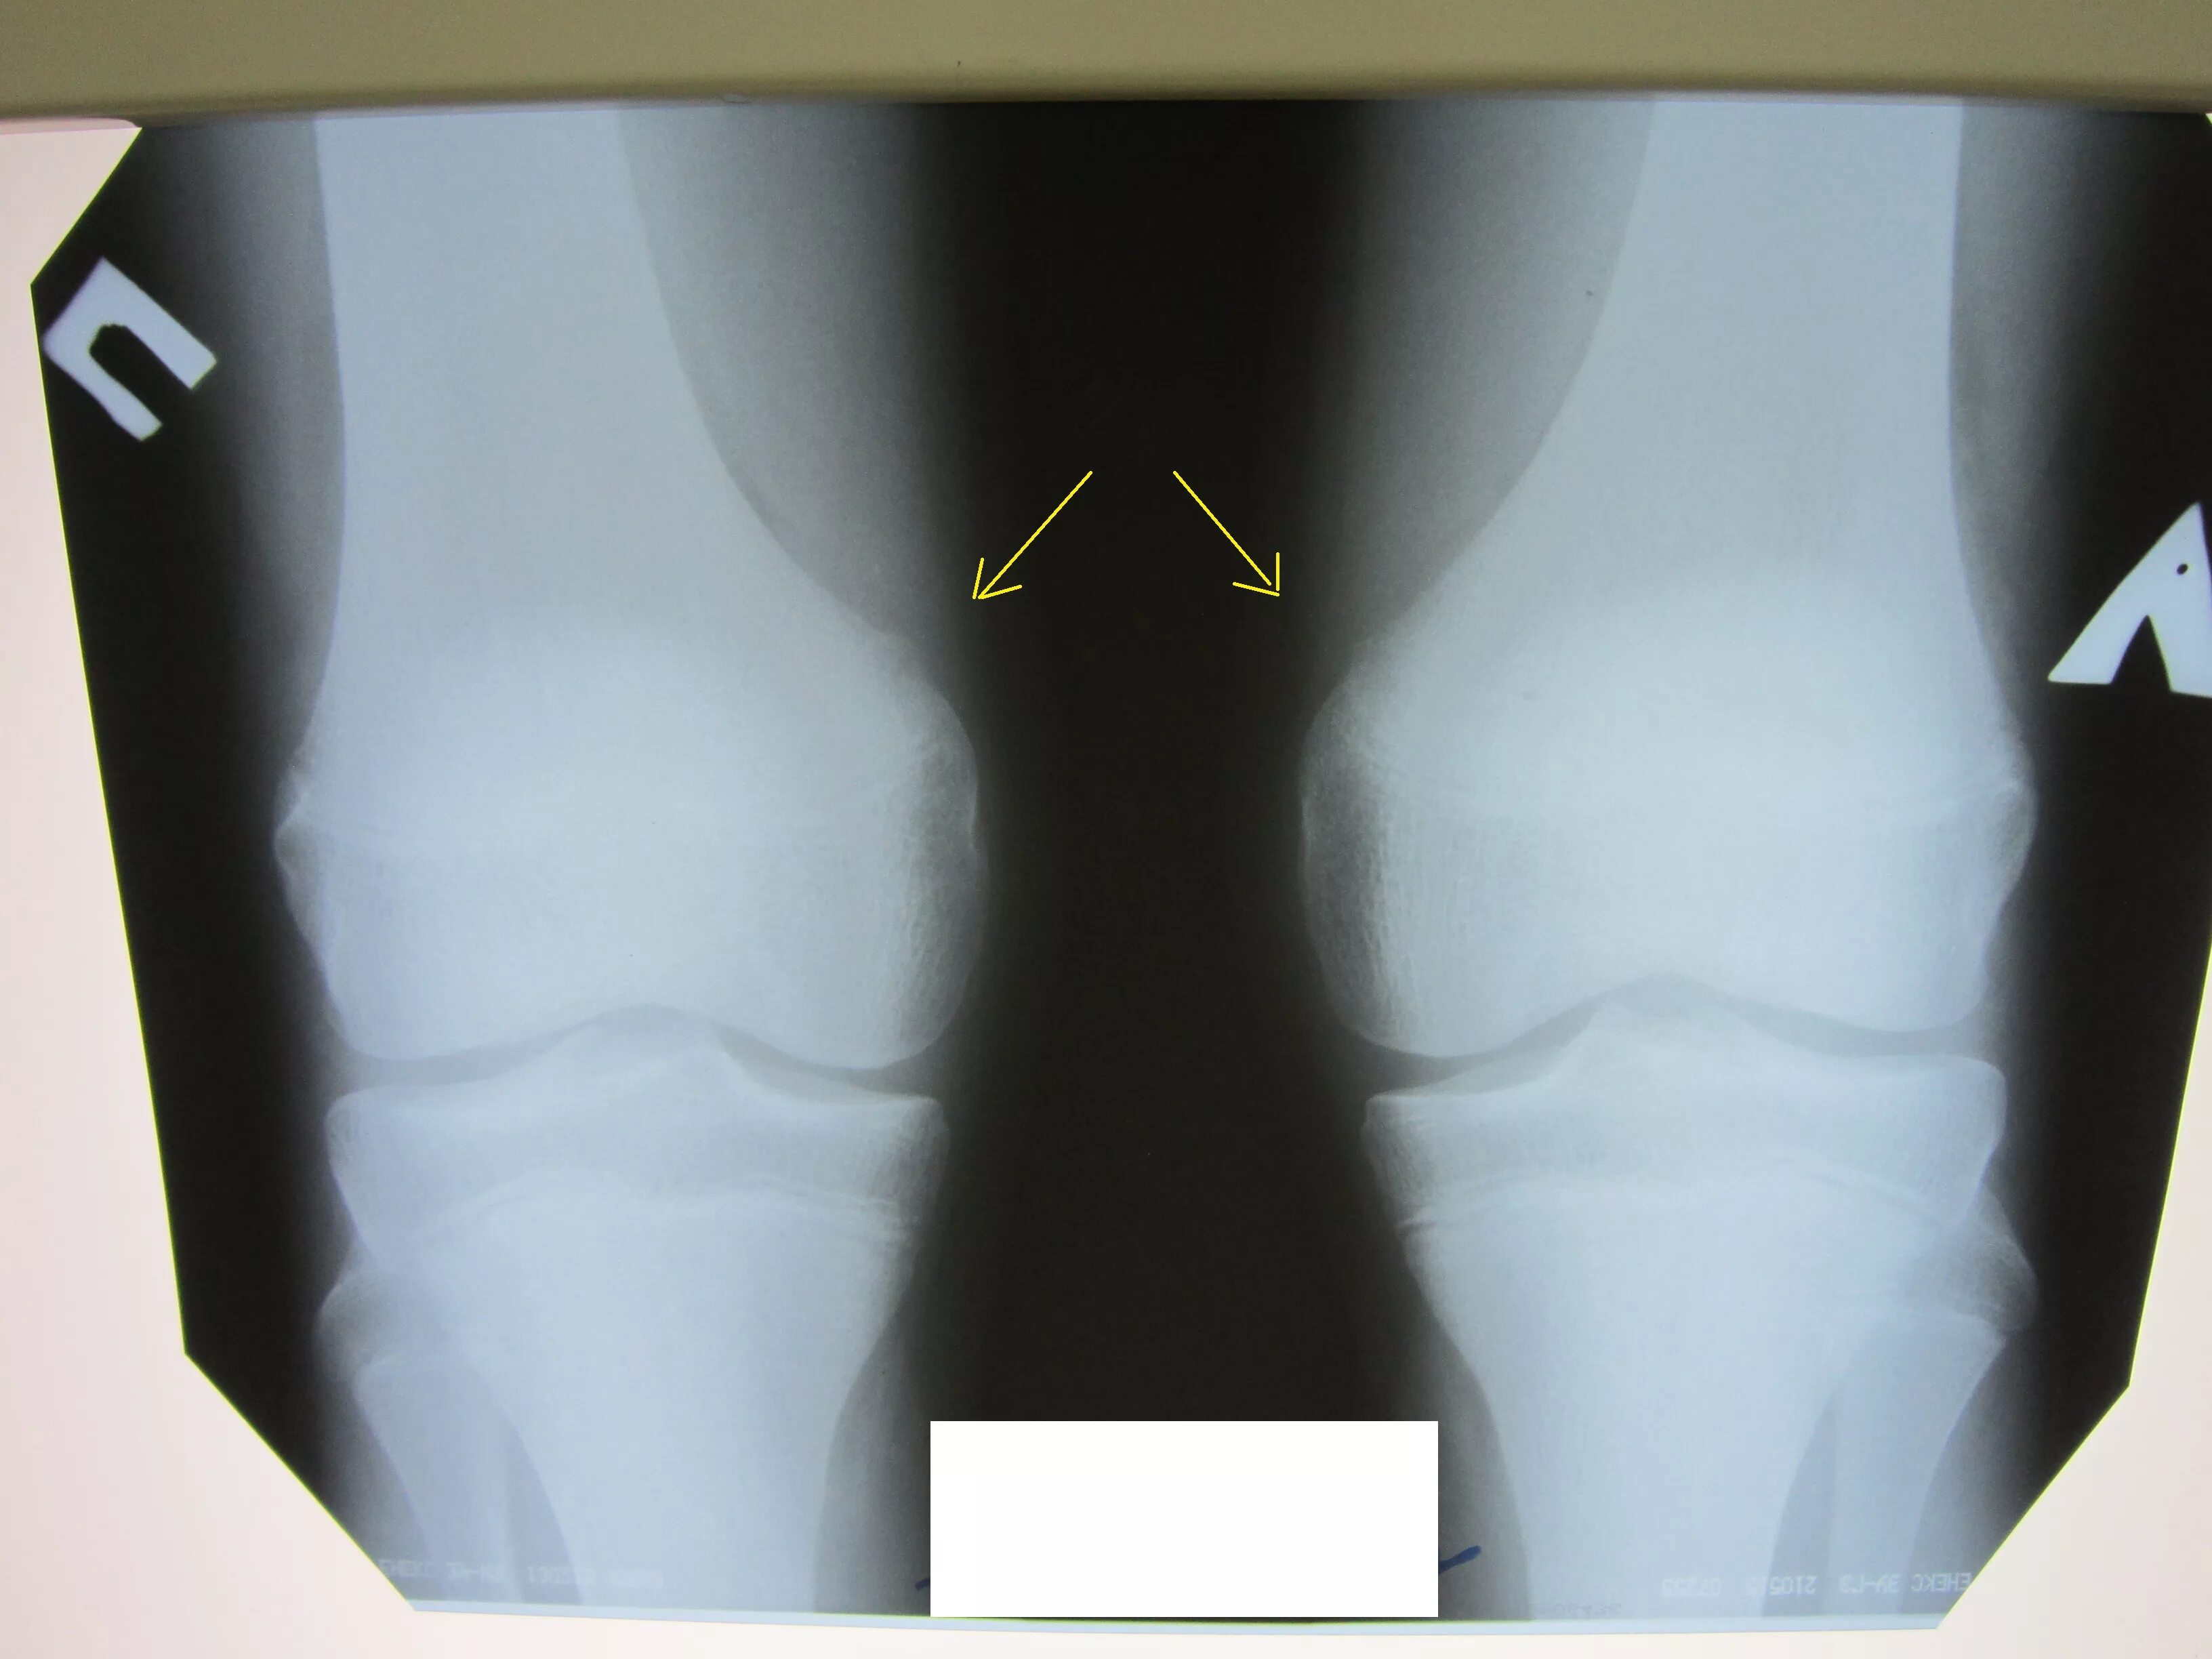

Экзостоз мкб 10